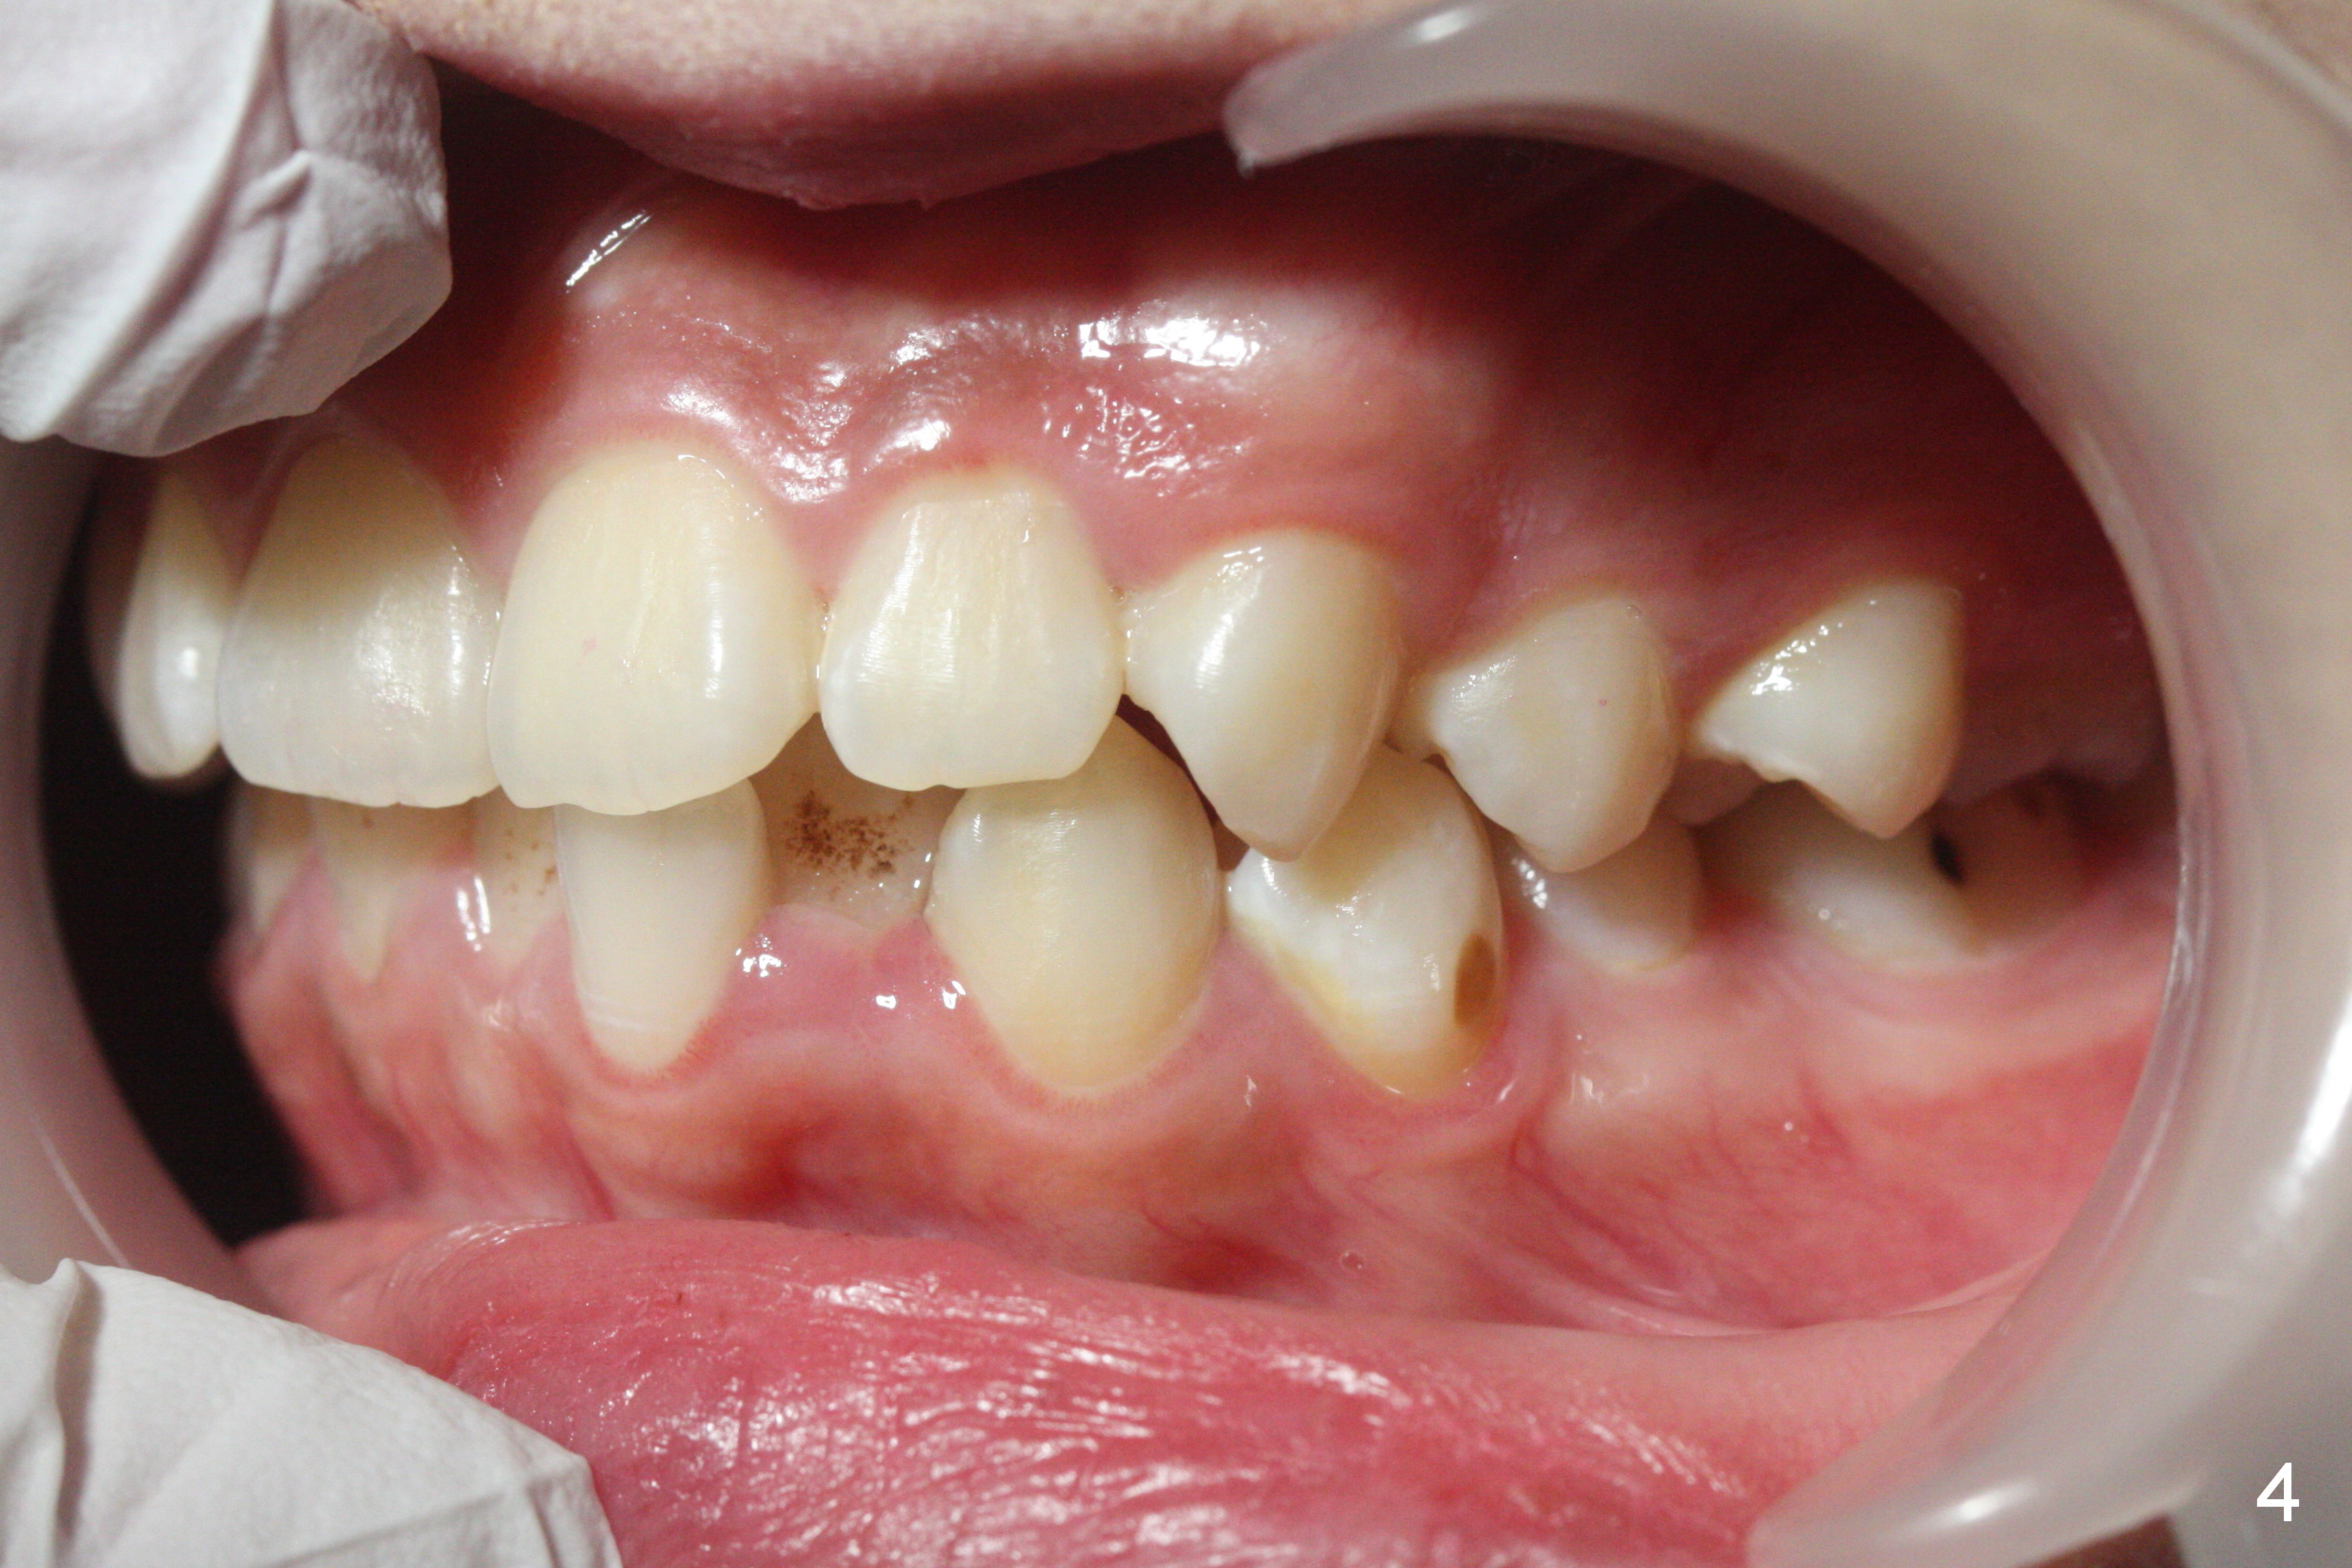

A 17-year-old woman will return for bracketing after caries control and deciduous tooth (Fig.6 arrowheads) extraction. Her profile is slightly protrusive (Fig.1,2). Crowding is more severe in the left posterior region (Fig.4) than the right one (Fig.3). The anterior crowding is also severe (Fig.5). Proximal reduction and use of power chain for constriction will be used instead of extraction of 4 bicuspids. Third molar extraction may have to be done prior to banding, especially for the lower right 2nd molar (Fig.7).

By looking at preop models (Fig.8-13), do you think whether extraction is a better option than non-extraction? Class II occlusion on the right (Fig.8), Class I on the left (Fig.10). With extraction of the 1st bicuspids, the posterior occlusion could be normal with further anterior protrusion (Fig.11). The upper arch is rounded (Fig.12); without extraction, the arch may turn out to be U-shaped. The lower arch is more crowded (Fig.13). Without space, the lower right 2nd molar may not be uprighted (Fig.7).